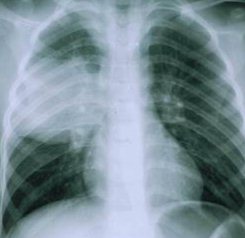

В большинстве случаев эхинококкоз протекает абсолютно бессимптомно. Нередко складывается ситуация, когда обнаружить эхинококкоз у детей и взрослых удается лишь при профилактических рентгенологических и ультразвуковых исследованиях. Если же гельминты прогрессируют до стадии кист, то они начинают сдавливать соседние органы и ткани. На этом этапе симптомы эхинококкоза проявляются более ярко. У пациентов наблюдаются различные симптомы, зависящие от места локализации финн. Так, к примеру, эхинококкоз печени сопровождается:

Легочная форма эхинококкоза приводит к возникновению болей в грудной клетке, кашля, одышки. Если у человека развивается эхинококкоз головного мозга симптомы имеют неврологическую природу. Чаще всего пациенты страдают от параличей, парезов, судорожных припадков и психических расстройств.

Наличие гельминтов в организме человека подтверждается с помощью визуализирующих лабораторных методов исследования. Как правило, врачи используют для этого рентген, МРТ, КТ и УЗИ. Ранее, наряду с перечисленными методиками, применялась и пункционная биопсия кисты, однако, в наши дни ее считают опасной, поскольку в ходе процедуры может произойти распространение паразитов в окружающие органы и ткани. Также для диагностики эхинококкоза не используются иммунологические методы, что связано с их низкой информативностью.